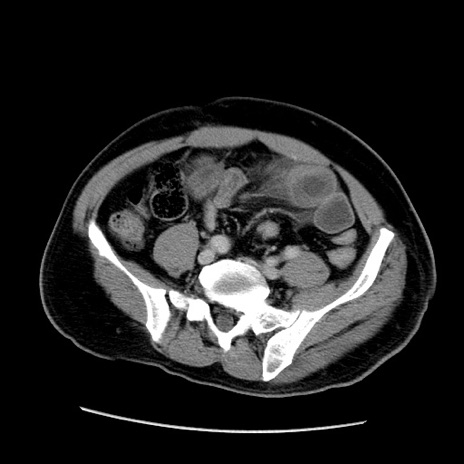

症例22(横断像)

【症例】50歳代男性

【主訴】腹痛

【現病歴】AVMからの被殻出血のため回復期リハ病棟入院中。 本日午後3時頃急に下腹部痛が出現した。

【既往歴】AVM、被殻出血、虫垂炎、高血圧

【身体所見】意識晴明、左半身不全麻痺、会話の理解は良好、36.5°C、腹部:膨隆、全体に板状硬、下腹部正中に圧痛点あり、反跳痛-、筋性防御不明、右下腹部にope scar

【データ】WBC 9400、CRP 0.06